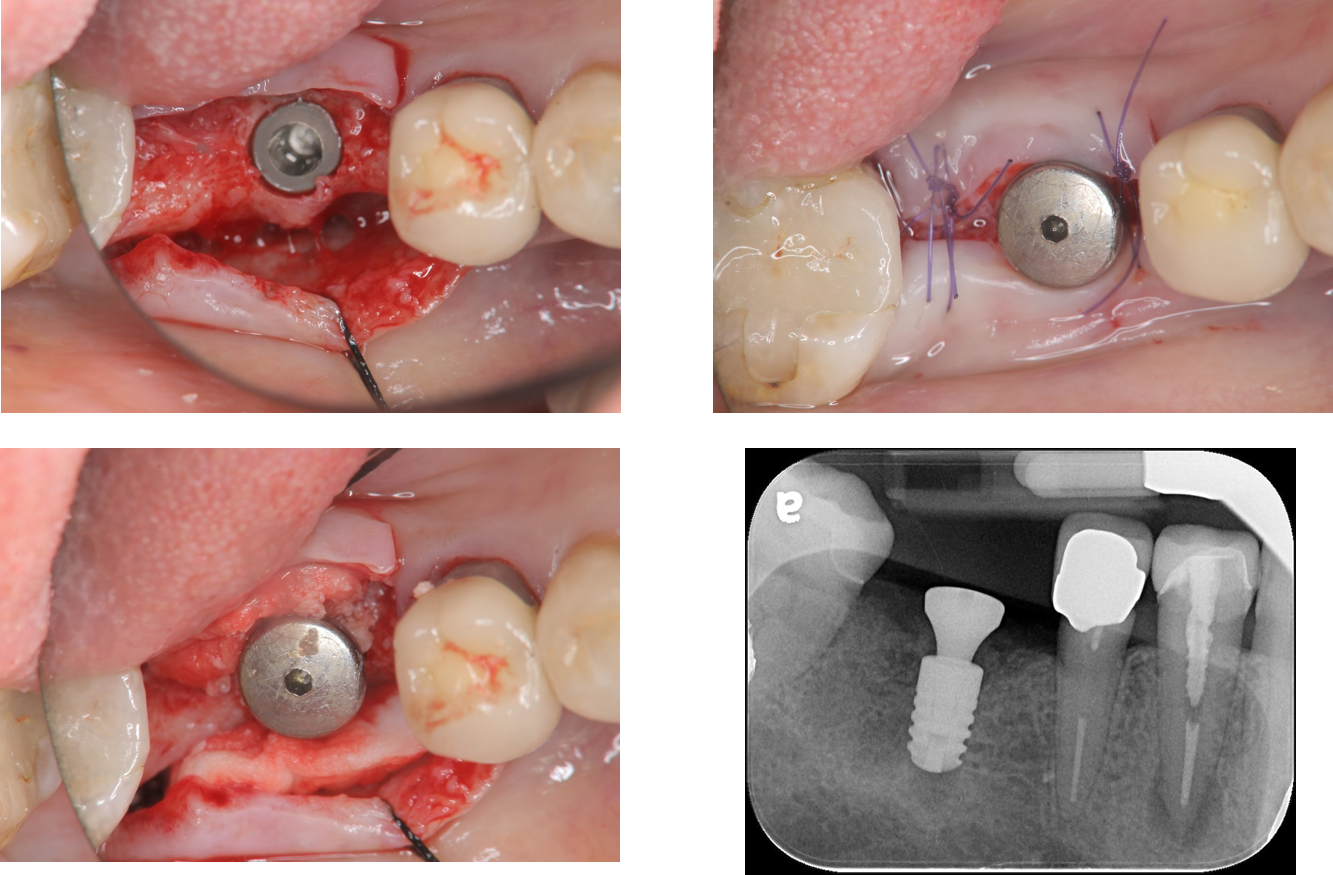

治療後,口內適應良好

治療後,植體周圍健康

術前、術後比較

使用單顆植牙,不需修磨正常的牙齒,清潔更方便,且咬合更強。